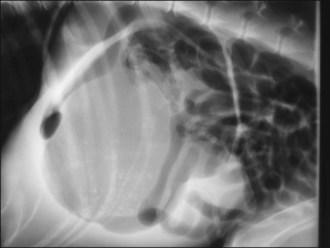

Acute GDV can usually be diagnosed on the basis of history, signalment and physical examination; radiography is generally not required. However, radiography may allow differentiation of gastric dilatation alone from gastric dilatation with volvulus. Radiography should not be performed until after fluid therapy and analgesia have been commenced and only if the patient is compliant as is usually the case. Radiography may be performed during the initial fluid resuscitation but should not delay gastric decompression. A single radiograph with the patient in right lateral recumbency is all that is typically required. Examples of radiographic findings are shown in Figures 29.3-29.6.

Figure 29.6 Right lateral abdominal radiograph showing gastric dilatation with volvulus and perforation of the stomach wall. Free air is visible within the abdominal cavity.